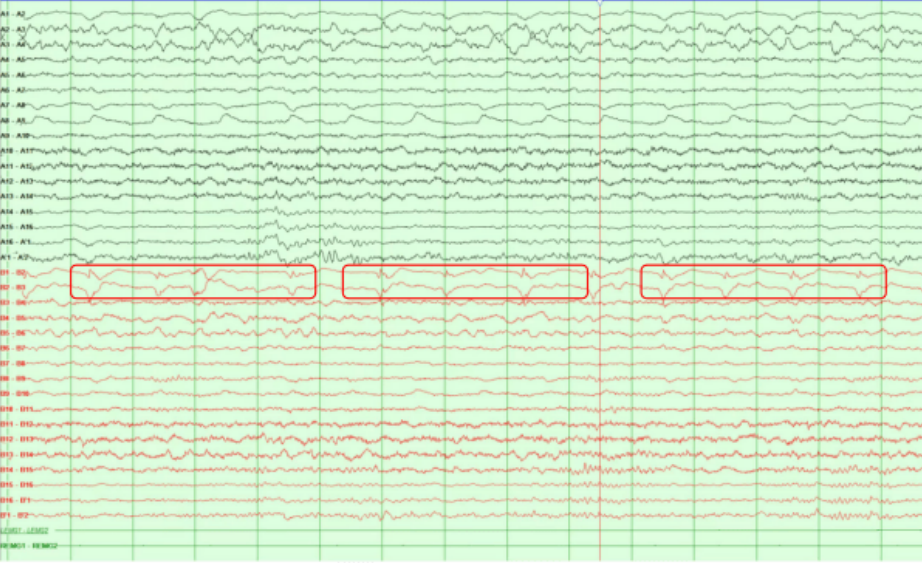

头皮脑电图并未监测到异常的放电

SEEG显示脑电图并监测到异常的放电